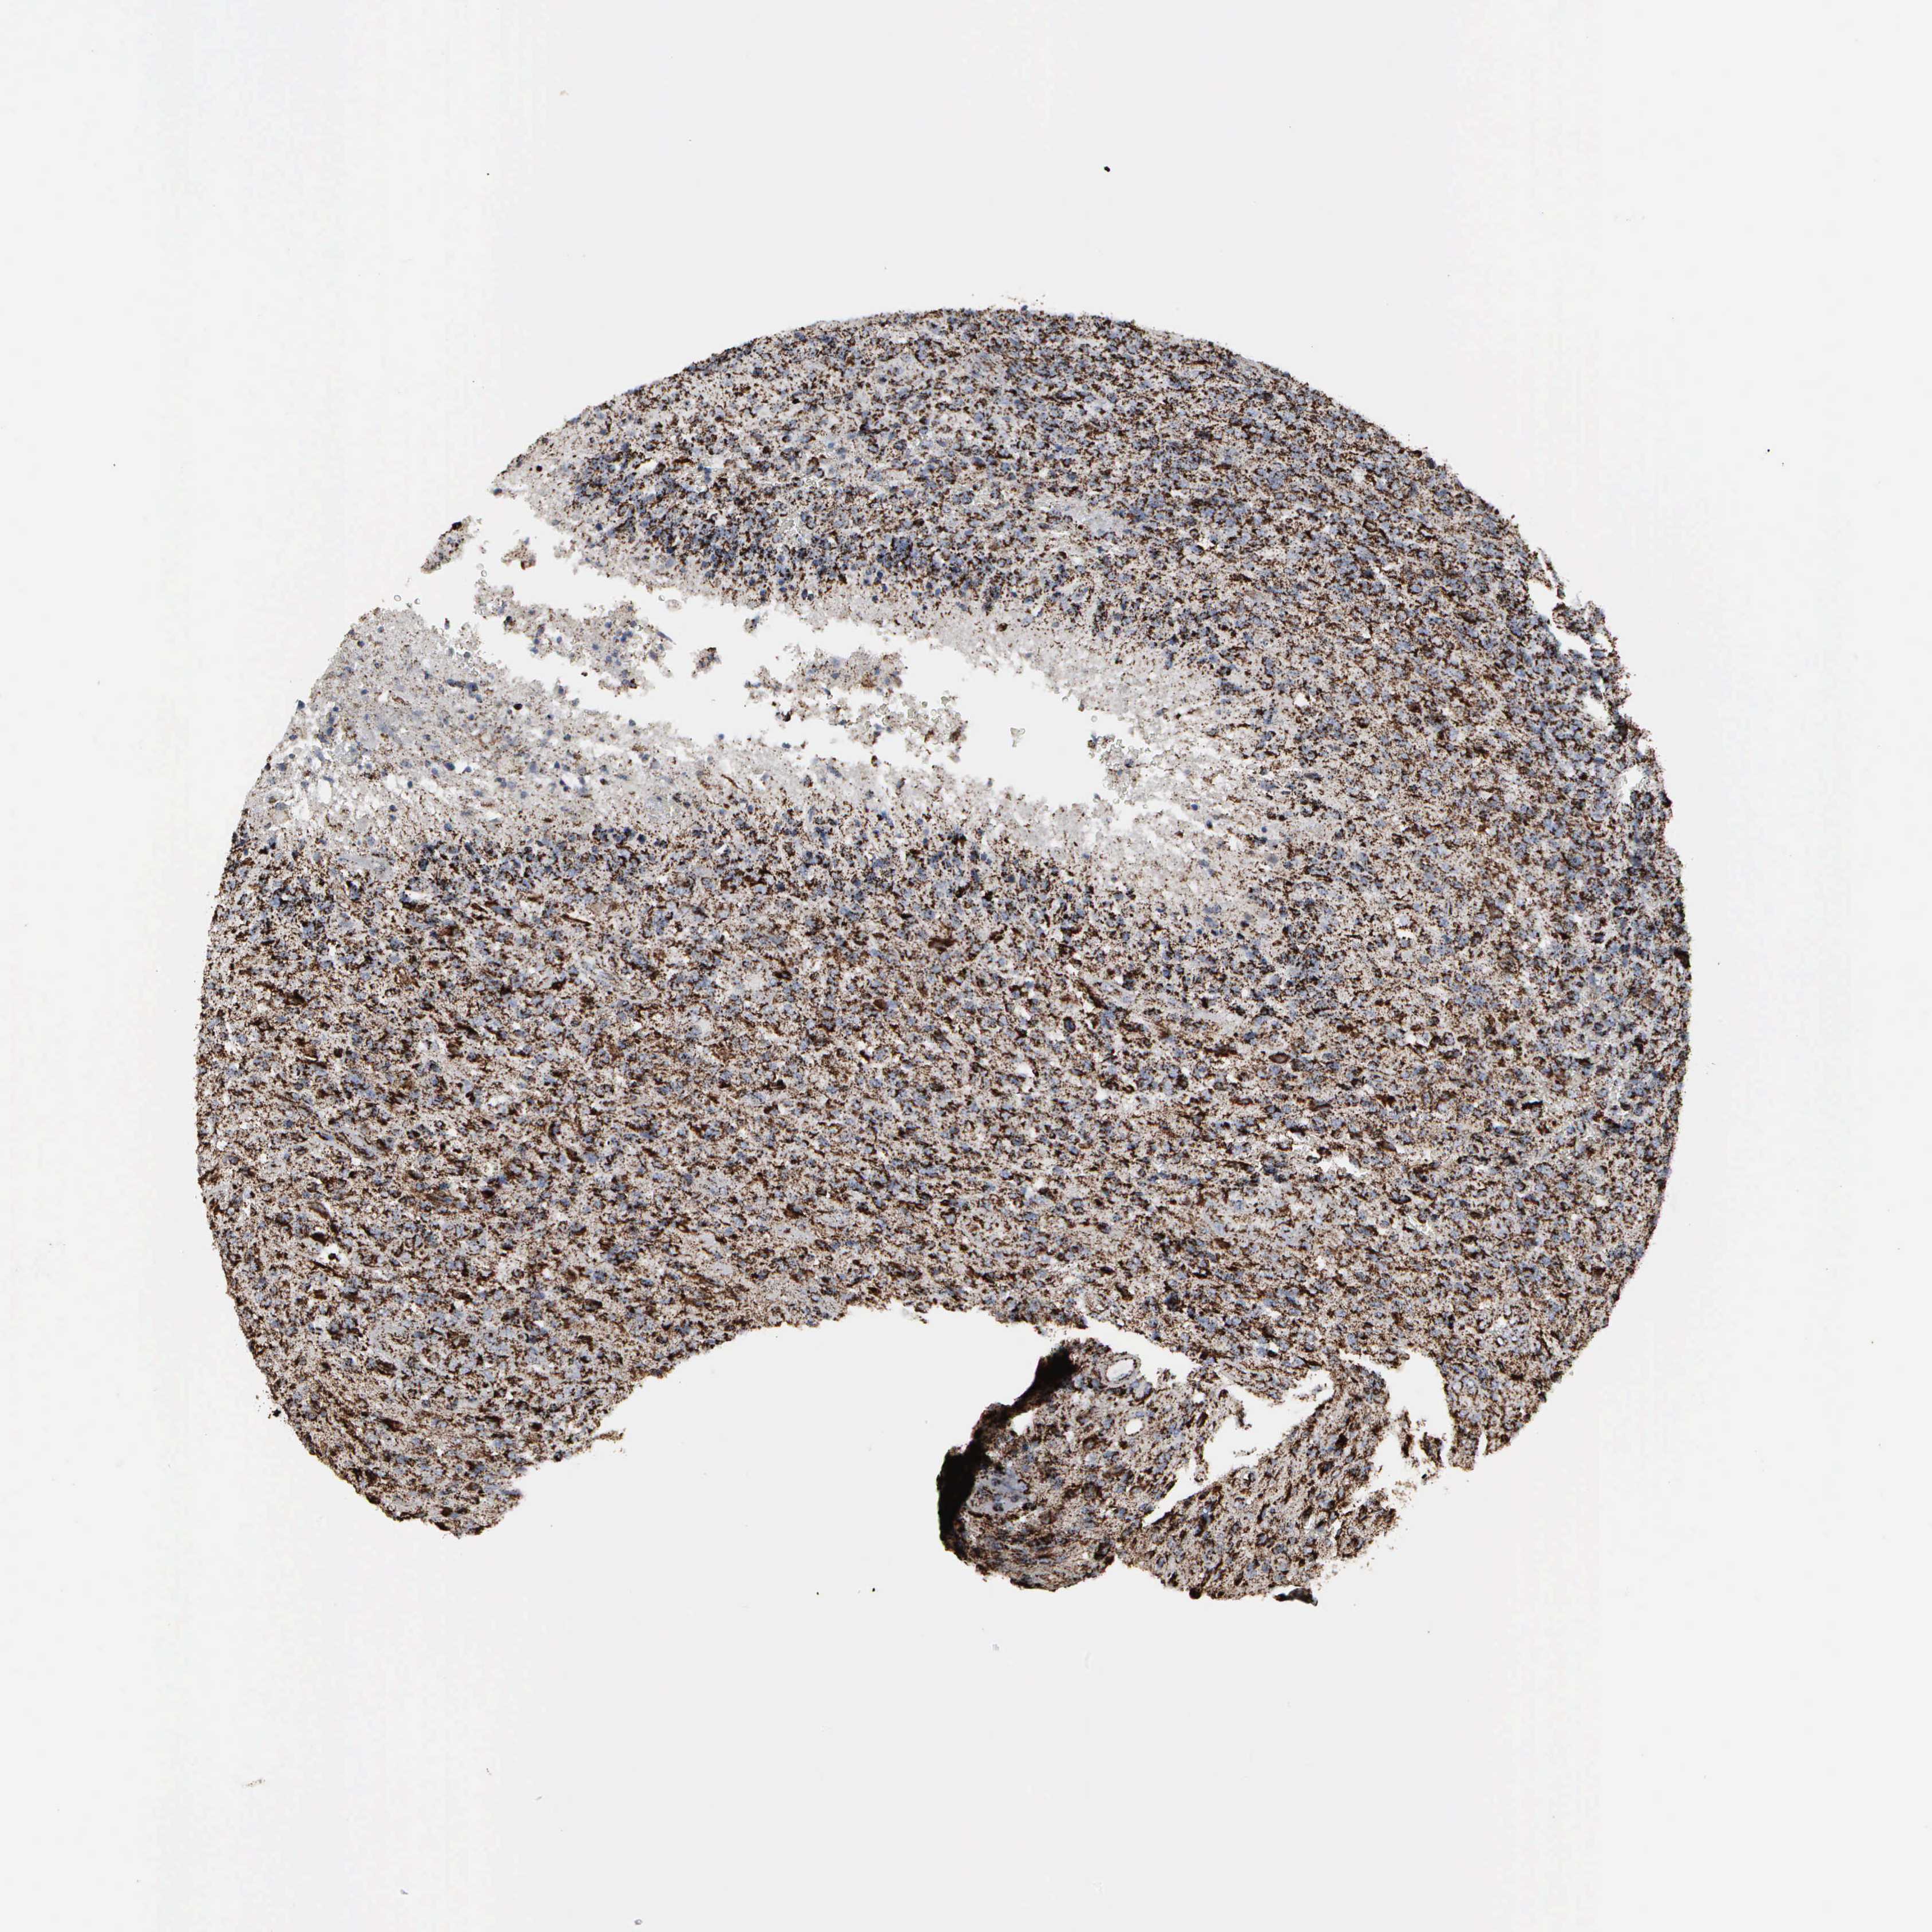

GLIOMA - Protein expressioni

A mouse-over function shows sample information and annotation data. Click on an image to view it in a full screen mode. Samples can be filtered based on level of antibody staining by selecting one or several of the following categories: high, medium, low and not detected. The assay and annotation is described here.

Note that samples used for immunohistochemistry by the Human Protein Atlas do not correspond to samples in the TCGA dataset.

Antibody stainingi

Antibody staining in the annotated cell types in the current human tissue is reported as not detected, low, medium, or high, based on conventional immunohistochemistry profiling in selected tissues. This score is based on the combination of the staining intensity and fraction of stained cells.

Each image is clickable and will lead to virtual microscopy that enables deeper exploration of all samples and also displays staining intensity scores, fraction scores and subcellular localization as well as patient and tissue information for each sample.

Antibody HPA000898

Antibody CAB005219

Staining

High

Medium

Low

Not detected

Intensity

Strong

Moderate

Weak

Negative

Quantity

>75%

75%-25%

<25%

None

Location

Nuclear

Cytoplasmic/membranous

Cytoplasmic/membranous,nuclear

Glioma, malignant, High grade

Glioma, malignant, Low grade